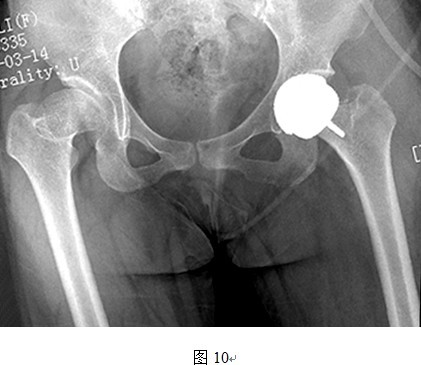

(1)头和臼假体之间有时很难良好匹配

DDH患者的髋臼发育不规律,头臼的匹配程度远远差于正常髋关节,而THRA的头臼假体间是一对一大小匹配,所以对于发育偏小的髋臼,按照髋臼侧决定THRA假体套件大小会出现股骨头过度磨锉,造成切迹;而按照股骨侧决定假体套件大小则会造成髋臼过度磨锉,大量骨质丢失,影响稳定性(图7、8所示即为以股骨侧决定假体大小时,髋臼侧出现过度磨锉,以致锉穿髋臼底部)。同样道理,对于发育偏大的髋臼,按照髋臼侧选择假体大小会造成人为的股骨颈缩窄(图9中所示病例以髋臼侧决定假体大小,导致股骨侧假体过大,反衬出股骨颈细小),而按照股骨侧决定假体型号则可能会出现髋臼软骨磨锉不充分,也可能影响髋臼假体稳定性(图10中所示病例以股骨侧选择假体大小,原始髋臼对于臼杯假体相对偏大,臼杯边缘的软骨尚未充分磨锉)。

图中所示,按照股骨侧决定假体大小原则,匹配的髋臼假体较原始臼来说过小,髋臼磨挫不充分,假体与髋臼匹配不良。